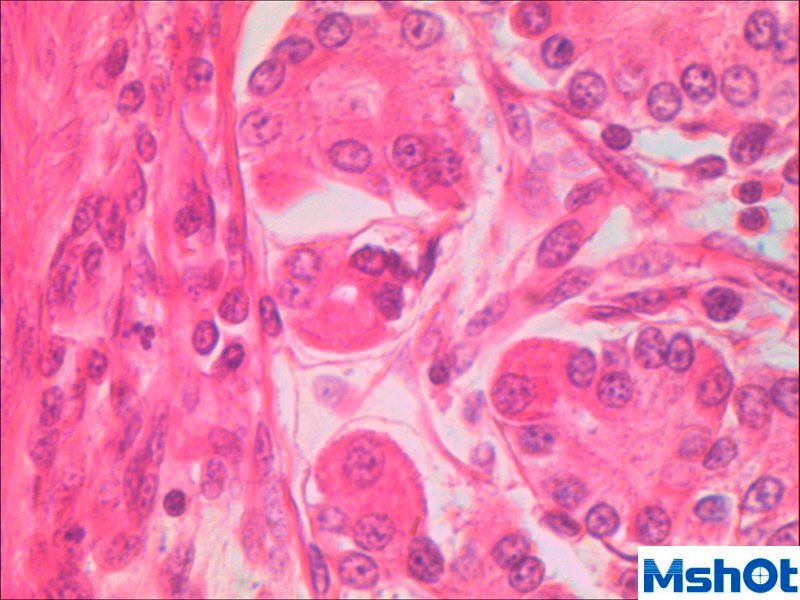

數(shù)碼攝像系統(tǒng):500萬像素數(shù)碼成像系統(tǒng),USB2.0高速接口。5幀/秒(2592x1944),19幀/秒(640x480),隨機(jī)配送界面友好的圖像分析軟件;